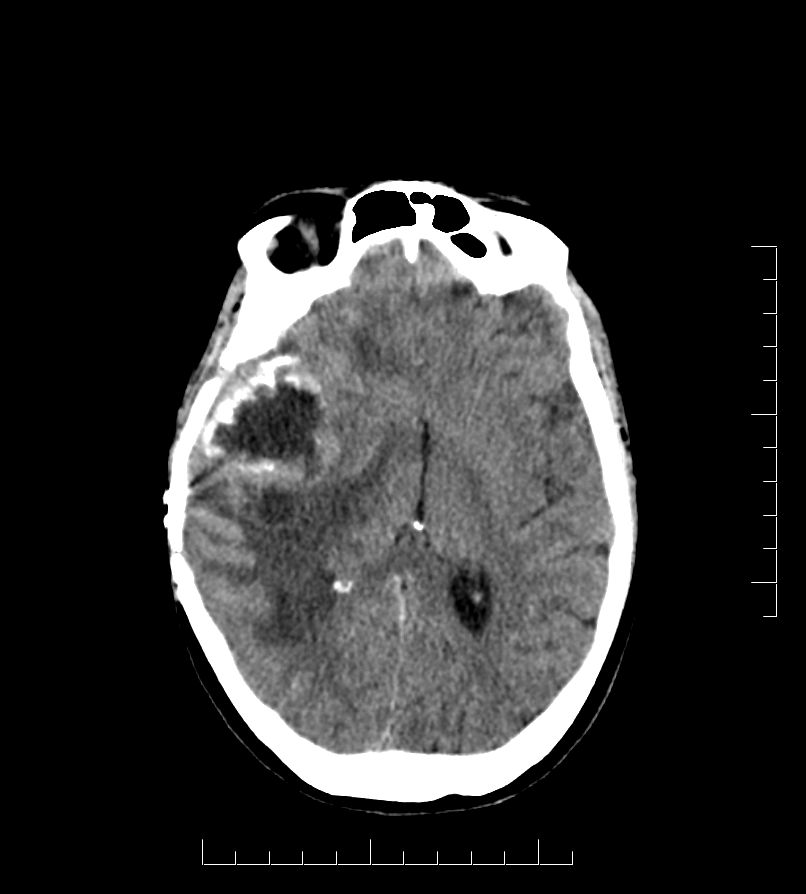

Submission_25_DC_Eaton_CT (1).…